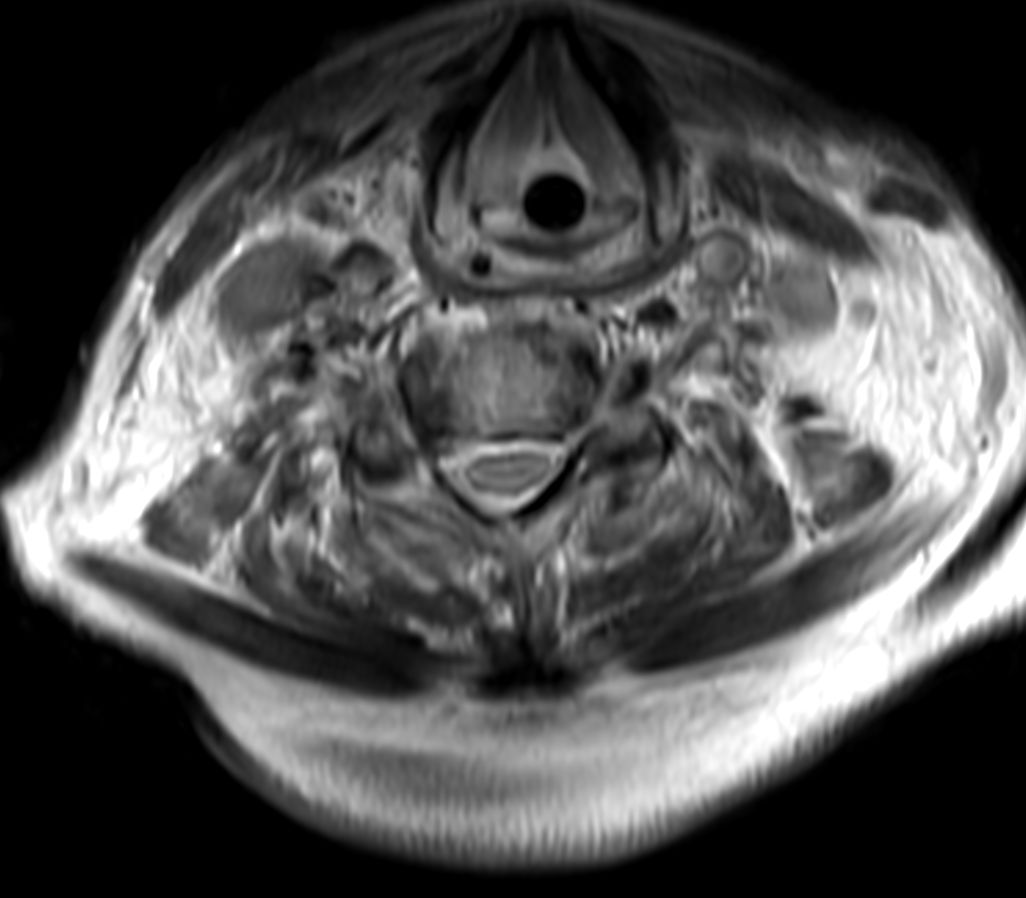

Cervical Spine - Cord lesion

T2w TSE MultiVane XD